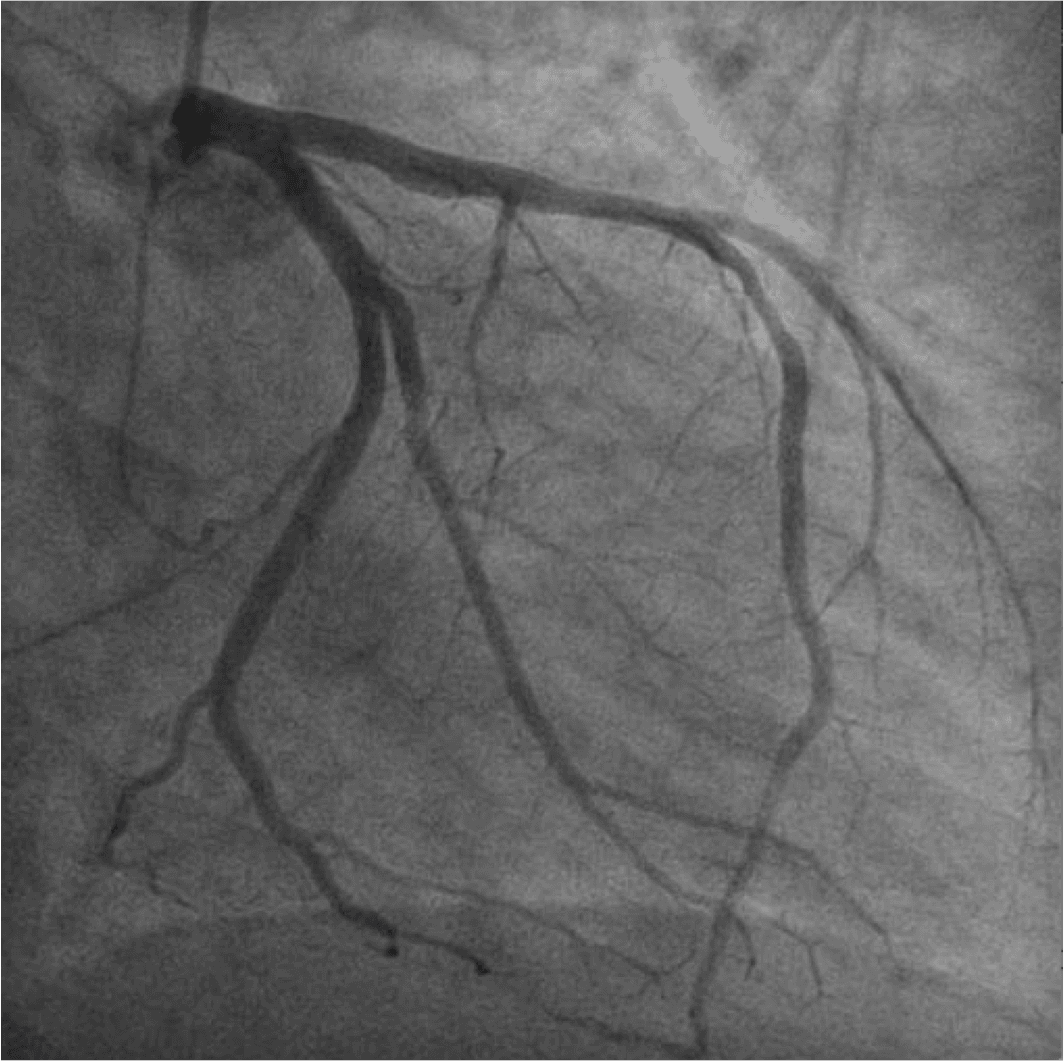

Em pacientes uniarteriais, a realização de testes não invasivos permite determinar o significado funcional da estenose coronária e correlacionar com a angiografia de forma simples e acurada.